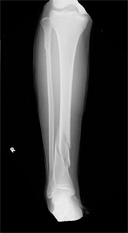

下腿骨折(すねの骨折)

バイクや自転車など交通事故で直接下腿をぶつけたりねじったりした時に生じる骨折です。

早期社会復帰のために手術が選択されることが多いものです。

• 画像:下腿骨折

(術前)